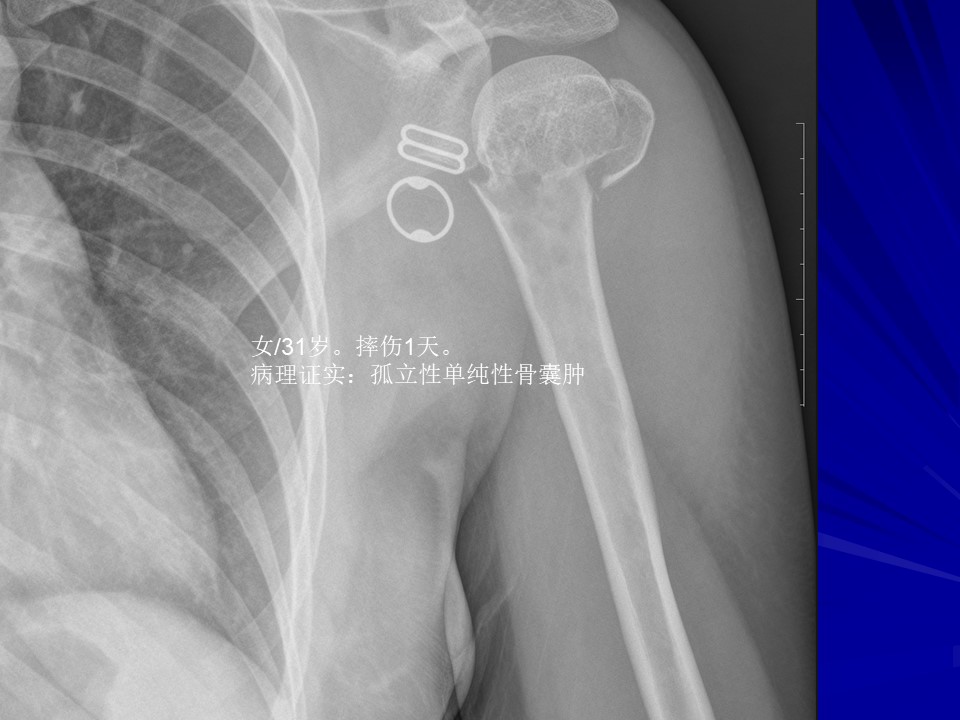

“常见骨肿瘤的X线诊断” 的相关文章